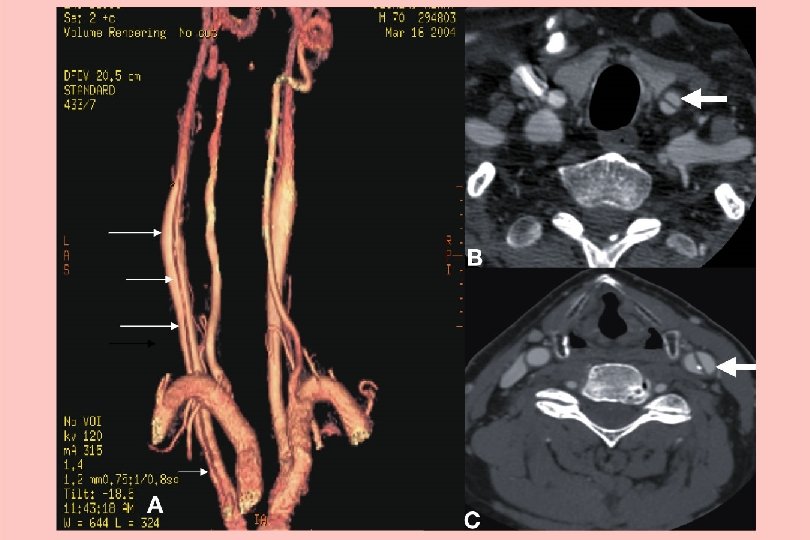

Temporal arteritis • Can be bilateral • Systemically unwell • Tender artery with allodynia • CRP better than ESR • Problem with skip lesions